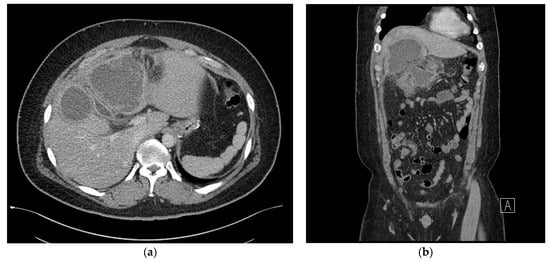

The abscess was effectively drained, and the right upper abdominal tenderness improved after 3 days (Figure 4a,b). However, a severe cough developed, and percutaneous drainage was performed for right pleural effusion. Chest CT was performed the following day as the cough did not sufficiently improve. Chest CT showed that the subhepatic abscess had markedly reduced, but the pleural effusion was multiloculated and had not been sufficiently drained. We drained the remaining pleural effusion through chest tubing.

Figure 4. (a) Axial view of the abdominal computed tomography (CT) scan showing the multiloculated fluid collection in the subhepatic space showing significant improvement. (b) Coronal view of abdominal computed tomography (CT) scan demonstrating improvement in the adjacent transverse colon wall thickening, which was associated with inflammatory changes.